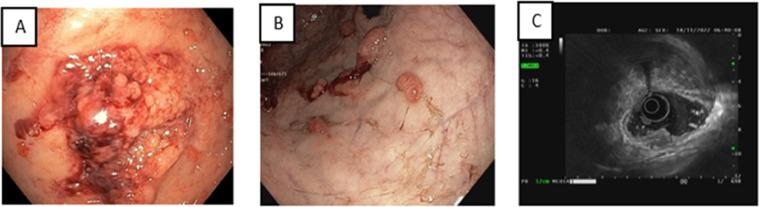

The coexistence of multiple primary malignant tumors in an organ is rare. This includes the extremely rarely reported combination of gastric adenocarcinoma and gastric MALT-type lymphoma as synchronous tumors. We describe a case of a 72-year-old man diagnosed with this combination. He had no remarkable medical history and came to our hospital because of discomfort in the gastric area. Although the biopsy revealed adenocarcinoma only, the microscopic findings after partial gastrectomy incidentally showed additional lymphoma that was subsequently confirmed by immunohistochemistry as MALT-type lymphoma. This case study and literature analysis aims to raise awareness of the possibility of synchronous malignant neoplasm in the stomach to enhance preoperative diagnosis.

一个器官内存在多种原发性恶性肿瘤的情况较为罕见。这包括极为罕见的胃腺癌与胃黏膜相关淋巴组织(MALT)型淋巴瘤同时发生的病例报道。我们描述了一名72岁男性被诊断为此种组合病例。他既往无显著病史,因胃部不适前来我院就诊。尽管活检仅显示为腺癌,但部分胃切除术后的显微镜检查结果意外发现了额外的淋巴瘤,随后经免疫组织化学证实为MALT型淋巴瘤。本病例研究及文献分析旨在提高对胃内同时发生恶性肿瘤可能性的认识,以加强术前诊断。